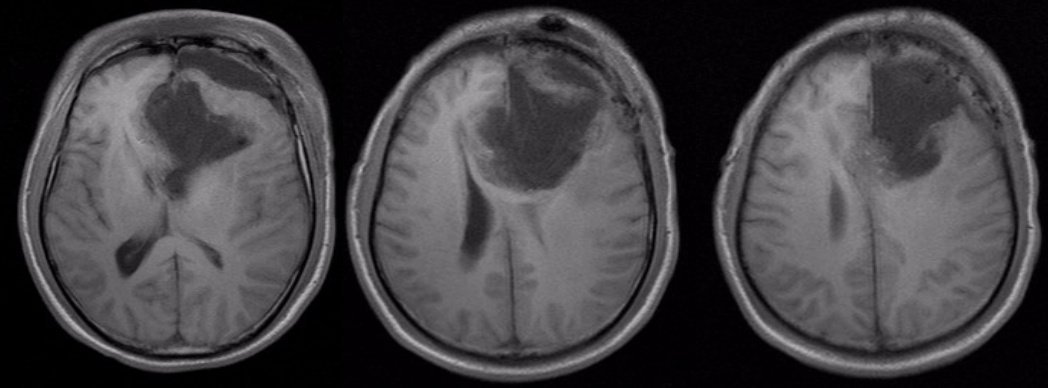

术前头颅MRI平扫加增强